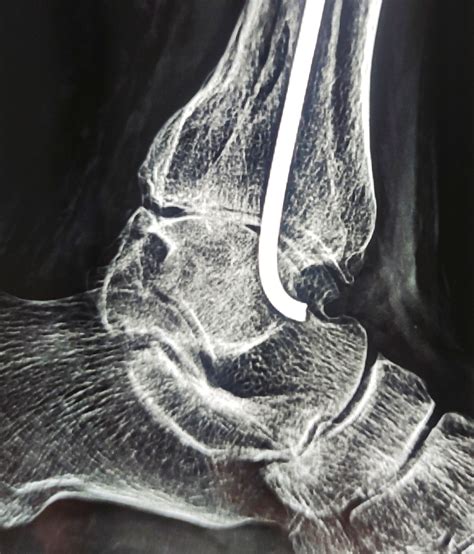

Tendo achilles tear – Best Orthopedic doctor in Jaipur

Considering Tendo Achilles surgery? Learn about the procedure, recovery timeline, and rehabilitation protocols. This guide covers surgical techniques for repairing a torn Achilles tendon, minimizing downtime, and regaining mobility. Discover expert advice on post-operative care and physical therapy exercises to ensure a successful return to activity following your Achilles tendon repair.